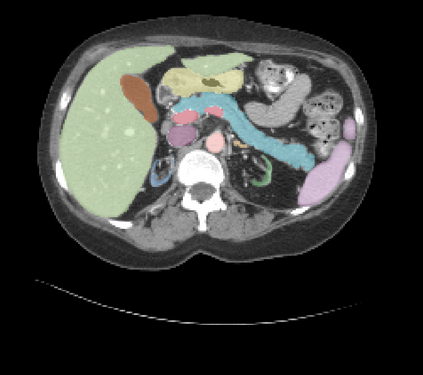

It is imperative to ensure the robustness of deep learning models in critical applications such as, healthcare. While recent advances in deep learning have improved the performance of volumetric medical image segmentation models, these models cannot be deployed for real-world applications immediately due to their vulnerability to adversarial attacks. We present a 3D frequency domain adversarial attack for volumetric medical image segmentation models and demonstrate its advantages over conventional input or voxel domain attacks. Using our proposed attack, we introduce a novel frequency domain adversarial training approach for optimizing a robust model against voxel and frequency domain attacks. Moreover, we propose frequency consistency loss to regulate our frequency domain adversarial training that achieves a better tradeoff between model's performance on clean and adversarial samples. Code is publicly available at https://github.com/asif-hanif/vafa.